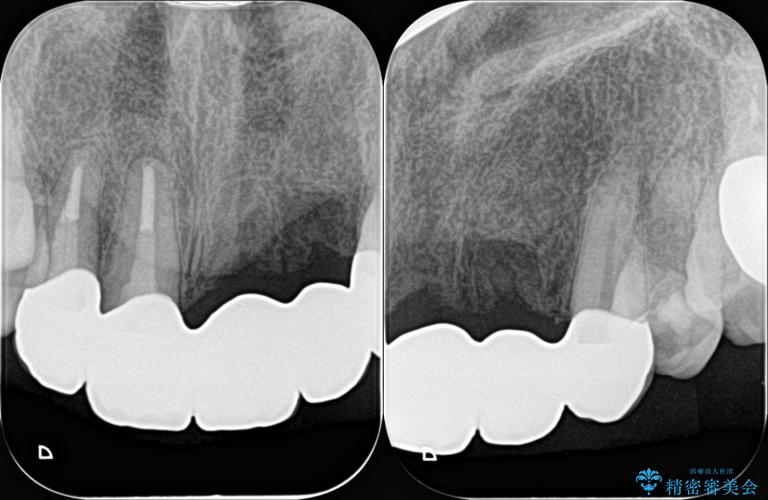

一見して問題ないように見える左側の2前歯は、セラミックを除去してみると亀裂や虫歯の再発が見られました。

抜歯時に可及的に歯肉のボリュームを保つよう骨充填材とコラーゲン製剤による填塞を行い審美的かつ機能的なブリッジとなるよう治療を進めます。

治療前

歯槽堤保存術を併用したブリッジ治療 治療前画像 歯槽堤保存術を併用したブリッジ治療 治療前画像 歯槽堤保存術を併用したブリッジ治療 治療前画像 歯槽堤保存術を併用したブリッジ治療 治療前画像 歯槽堤保存術を併用したブリッジ治療 治療前画像 歯槽堤保存術を併用したブリッジ治療 治療前画像 歯槽堤保存術を併用したブリッジ治療 治療前画像 歯槽堤保存術を併用したブリッジ治療 治療前画像 歯槽堤保存術を併用したブリッジ治療 治療前画像 歯槽堤保存術を併用したブリッジ治療 治療前画像